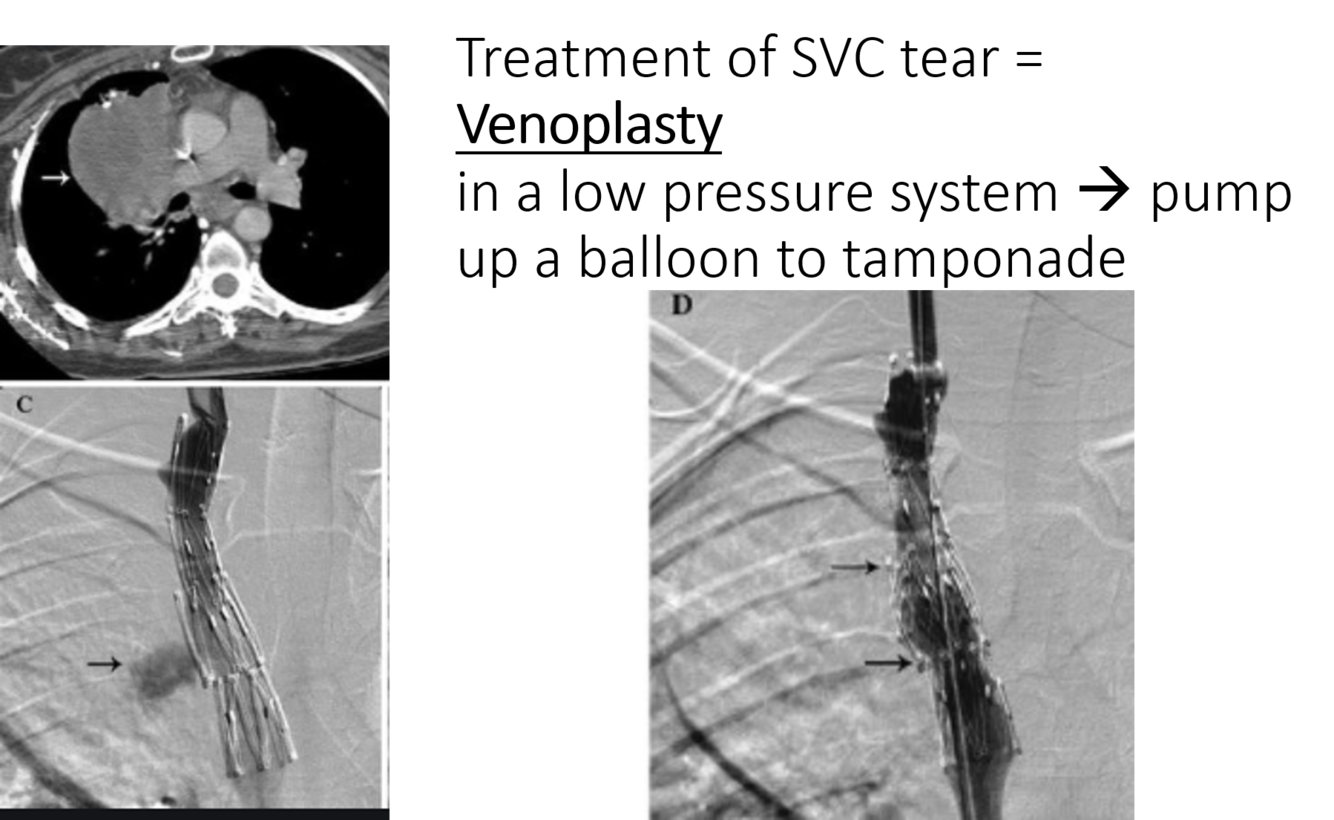

SVC syndrome may lead to dilated collaterals and edema –> airway compromise due to collateral vessels and swelling

treatment option = SVC stent placement